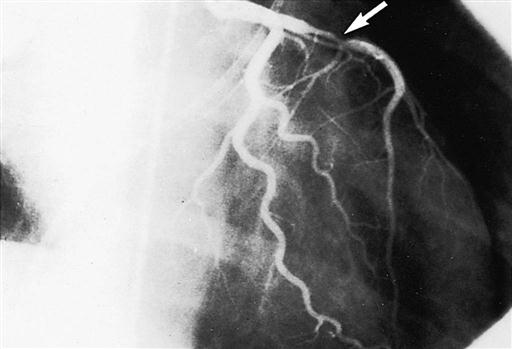

Cardiac catheterization provides definitive information about the extent and location of ischemic heart disease, acting as an adjunct to echocardiography to diagnose valvular heart disease (Kern, 2011). A radiopaque plastic catheter is inserted retrograde through the aortic valve into the left side of the heart by a percutaneous puncture or a cutdown to the vessels of the brachial artery (Sones technique) or the femoral artery (Judkins technique). The right side of the heart is approached percutaneously by the superior or inferior vena caval route. To perform coronary angiography that demonstrates intracoronary anatomy, a contrast medium is injected into the coronary ostia. Obstructions (Figure 25-12), flow, and distal perfusion are assessable. Ventriculography illustrates contractile weaknesses of the ventricles as well as shunting and regurgitation of blood. These studies enable assessment of the degree of myocardial dysfunction and planning for interventions such as CABG, valve repair or replacement, repair of congenital anomalies, and cardiac transplantation. The cardiologist can compute the orifice of a stenosed valve or determine the degree of regurgitation of an incompetent valve.